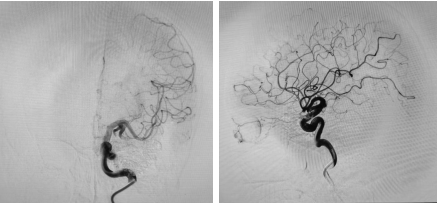

术后DSA

术中,在纪文军主任医师、张伟副主任医师、李涛副主任医师、赵乐副主任医师及麻醉手术科团队的紧密协作下,成功对王女士脑中的动静脉畸形多支供血血管进行了栓塞。手术历时两个多小时,顺利完成。术后复查脑血管造影显示,颅内动静脉畸形已完全栓塞。后期经过神经外科二病区医护团队精心的康复治疗与护理,王女士恢复良好,意识清晰,已能正常生活和工作。